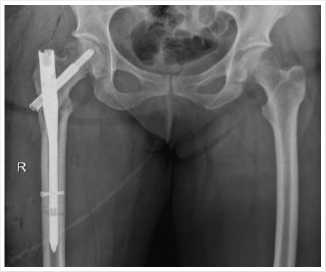

Больная К., 64 года доставлена в экстренном порядке бригадой скорой медицинской помощи в приемное отделение 24 ноября 2022 г. Из анамнеза травма бытовая упала на улице с высоты собственного роста на область правого бедра. При госпитализации в приемном отделении осмотрена травматологом. Жалобы на острую боль в правом бедре. При осмотре отмечается наружная ротация и незначительное укорочение правой нижней конечности, умеренный отек правого бедра. При пальпации определяется болезненность правого бедра, патологическая подвижность. Пассивные и активные движения в конечности резко болезненны. Пульсация сосудов нижней конечности не ослаблена. Чувствительность не нарушена. Больная госпитализирована в травматологическое отделение. Проведено инструментальное и лабораторное обследование и предоперационная подготовка. Выставлен диагноз закрытый перелом шейки правой бедренной кости Garden 2, Pauwels 1– рис. 1.

Рис. 1. Перелом шейки правой бедренной кости Garden 2, Pauwels 1.